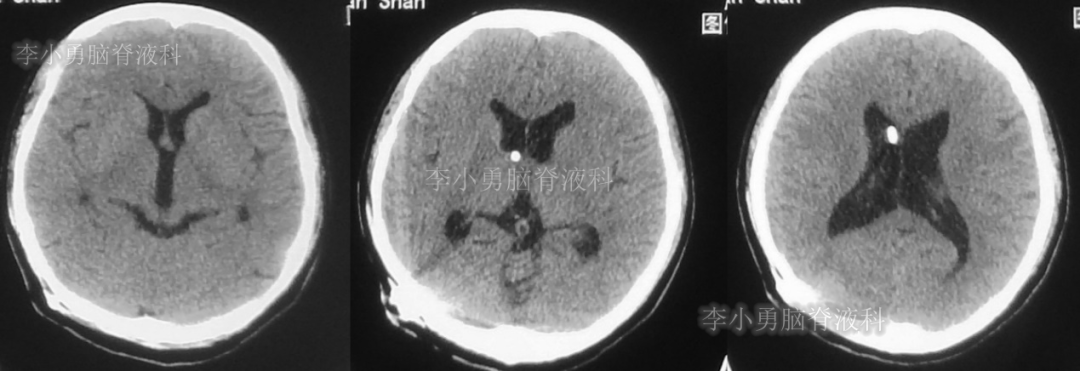

次日,即2018年11月11日,患者第2次到给予脑室腹腔分流术的医院,复查头颅CT(图-5)见脑积水仍严重。

图-5:2018年11月11日头颅CT

但第2次调压后2周,即2018年11月28日,再次到当地的第1家医院复查头颅CT(图-6)见脑积水缓解。

图-6:2018年11月28日头颅CT